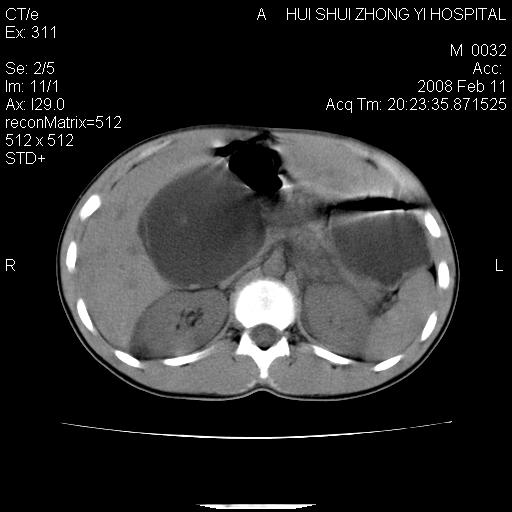

8年前曾在贵洲省人民医院b超诊断为肝内胆管结石。现腹痛剧烈,现发烧、头痛、恶心呕吐县医院b超示胆囊肿大大小159*46mm,囊内见6*5mm强回声光团,胆各总管内径56mm。提示:胆囊结石、急性胆囊炎、胆总管重度扩张。

胆囊结石.急性胆囊炎.重度胆管扩张.右侧胸腔少量积液,建议ct增强

考虑先天性胆管囊肿;胆囊增大并结石。右侧胸腔少量积液,建议ct增强。

caroli囊肿并囊内结石。胆囊增大并胆结石。典型!

先天性胆管囊肿,胆囊结石、胆囊增大,右侧少量胸腔积液。